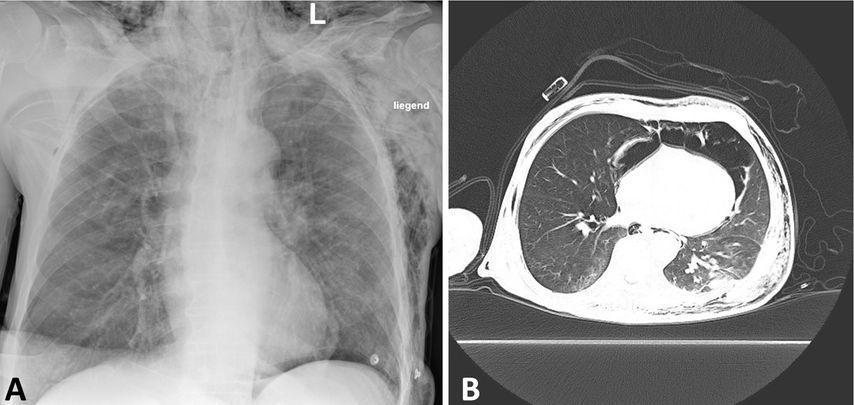

Abb. 1: Eine 25 Jahre alte Patientin nach seitlichem Aufprall mit linksseitiger Zwerchfellruptur und Migration der Oberbauchorgane in den Thorax. Koronare Schichten zeigen die Magenblase im linken Hemithorax (A). Axial ist das Ausmaß der Organmigration dargestellt (B). Lungenröntgen 4 Tage nach der unmittelbar posttraumatisch durchgeführten Rekonstruktion des Zwerchfells (C)